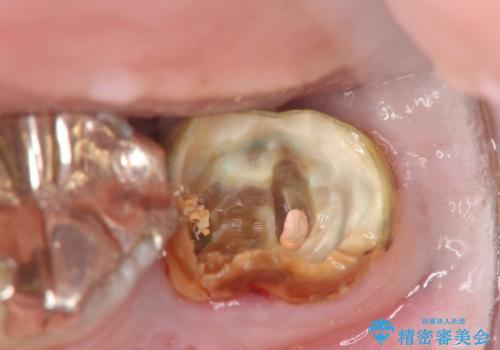

- 左下奥歯の咬合時疼痛を訴えて来院されました。

最後方臼歯周囲には大きな透過像が見られ、破折が強く疑われること抜歯が想定されることを理解していただき銀歯を除去したところ破折が認められたため抜歯を行いました。